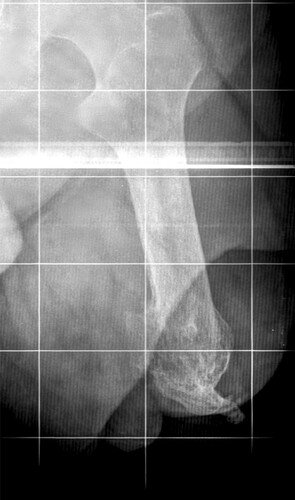

RX COTO SIDNEY RIBAS

Em 2005 sofrei um acidente grave de moto, onde tive meu braço esquerdo e minha perna esquerdos amputados no local.

Amputado, do braço esquerdo e perna esquerda, tenho extrema dificuldade para se adaptar com a prótese, mais por não ter o braço esquerdo me impossibilitou usar um par de muletas, ou a cadeira de rodas sozinho, desta forma mesmo com muitas dores e machucado eu me obriguei a usar a prótese.